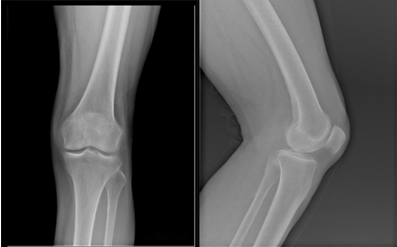

在医院护士的全程陪同下,蔡奶奶在一个上午的时间里,做完了所有检查。李龙付副主任确诊其为“左膝骨性关节炎和半月板损伤”,需通过关节镜冲洗清理左膝。蔡奶奶却非常排斥手术。为了尽量让其明白治疗的缘由和方法,李龙付副主任拿身边的东西来打比方,“您的膝盖,就好像瓷盆,用的时间长了,外层漆就会被磨光,露出了里面的瓷,经不起摔。您走路疼就是这个原因,严重的时候就需要换人工关节了。但是现在用关节镜做一个关节清理手术,用专业设备操作在膝盖打个小孔,就可以解决你现在的问题,还可以延长自身关节的使用寿命。”蔡奶奶起初还是不放心,又问了许多问题,李龙付副主任都一一解答,并且用通俗的语言让她安心。蔡奶奶终决定相信主任,接受手术。

李龙付副主任为蔡奶奶做完一系列辅助检查和术前准备,确认万无一失后,为蔡奶奶在腰麻下施行“左膝关节镜关节腔清理+半月板修整术”。关节镜手术术中切口小,医生需要凭借精细的器械在关节间隙内检查修复并且避免对关节造成磨损,因而对医生的要求是很高的。李龙付副主任利用关节镜将蔡奶奶关节面不平的部分磨平,将内侧半月板后角破裂的部分咬除,四十分钟后,手术顺利完成。医院为蔡奶奶提供规范的术后康复指导,术后三天其就能下床活动,关节功能恢复如初,7月14日顺利出院。蔡奶奶及家属均对手术表示满意。